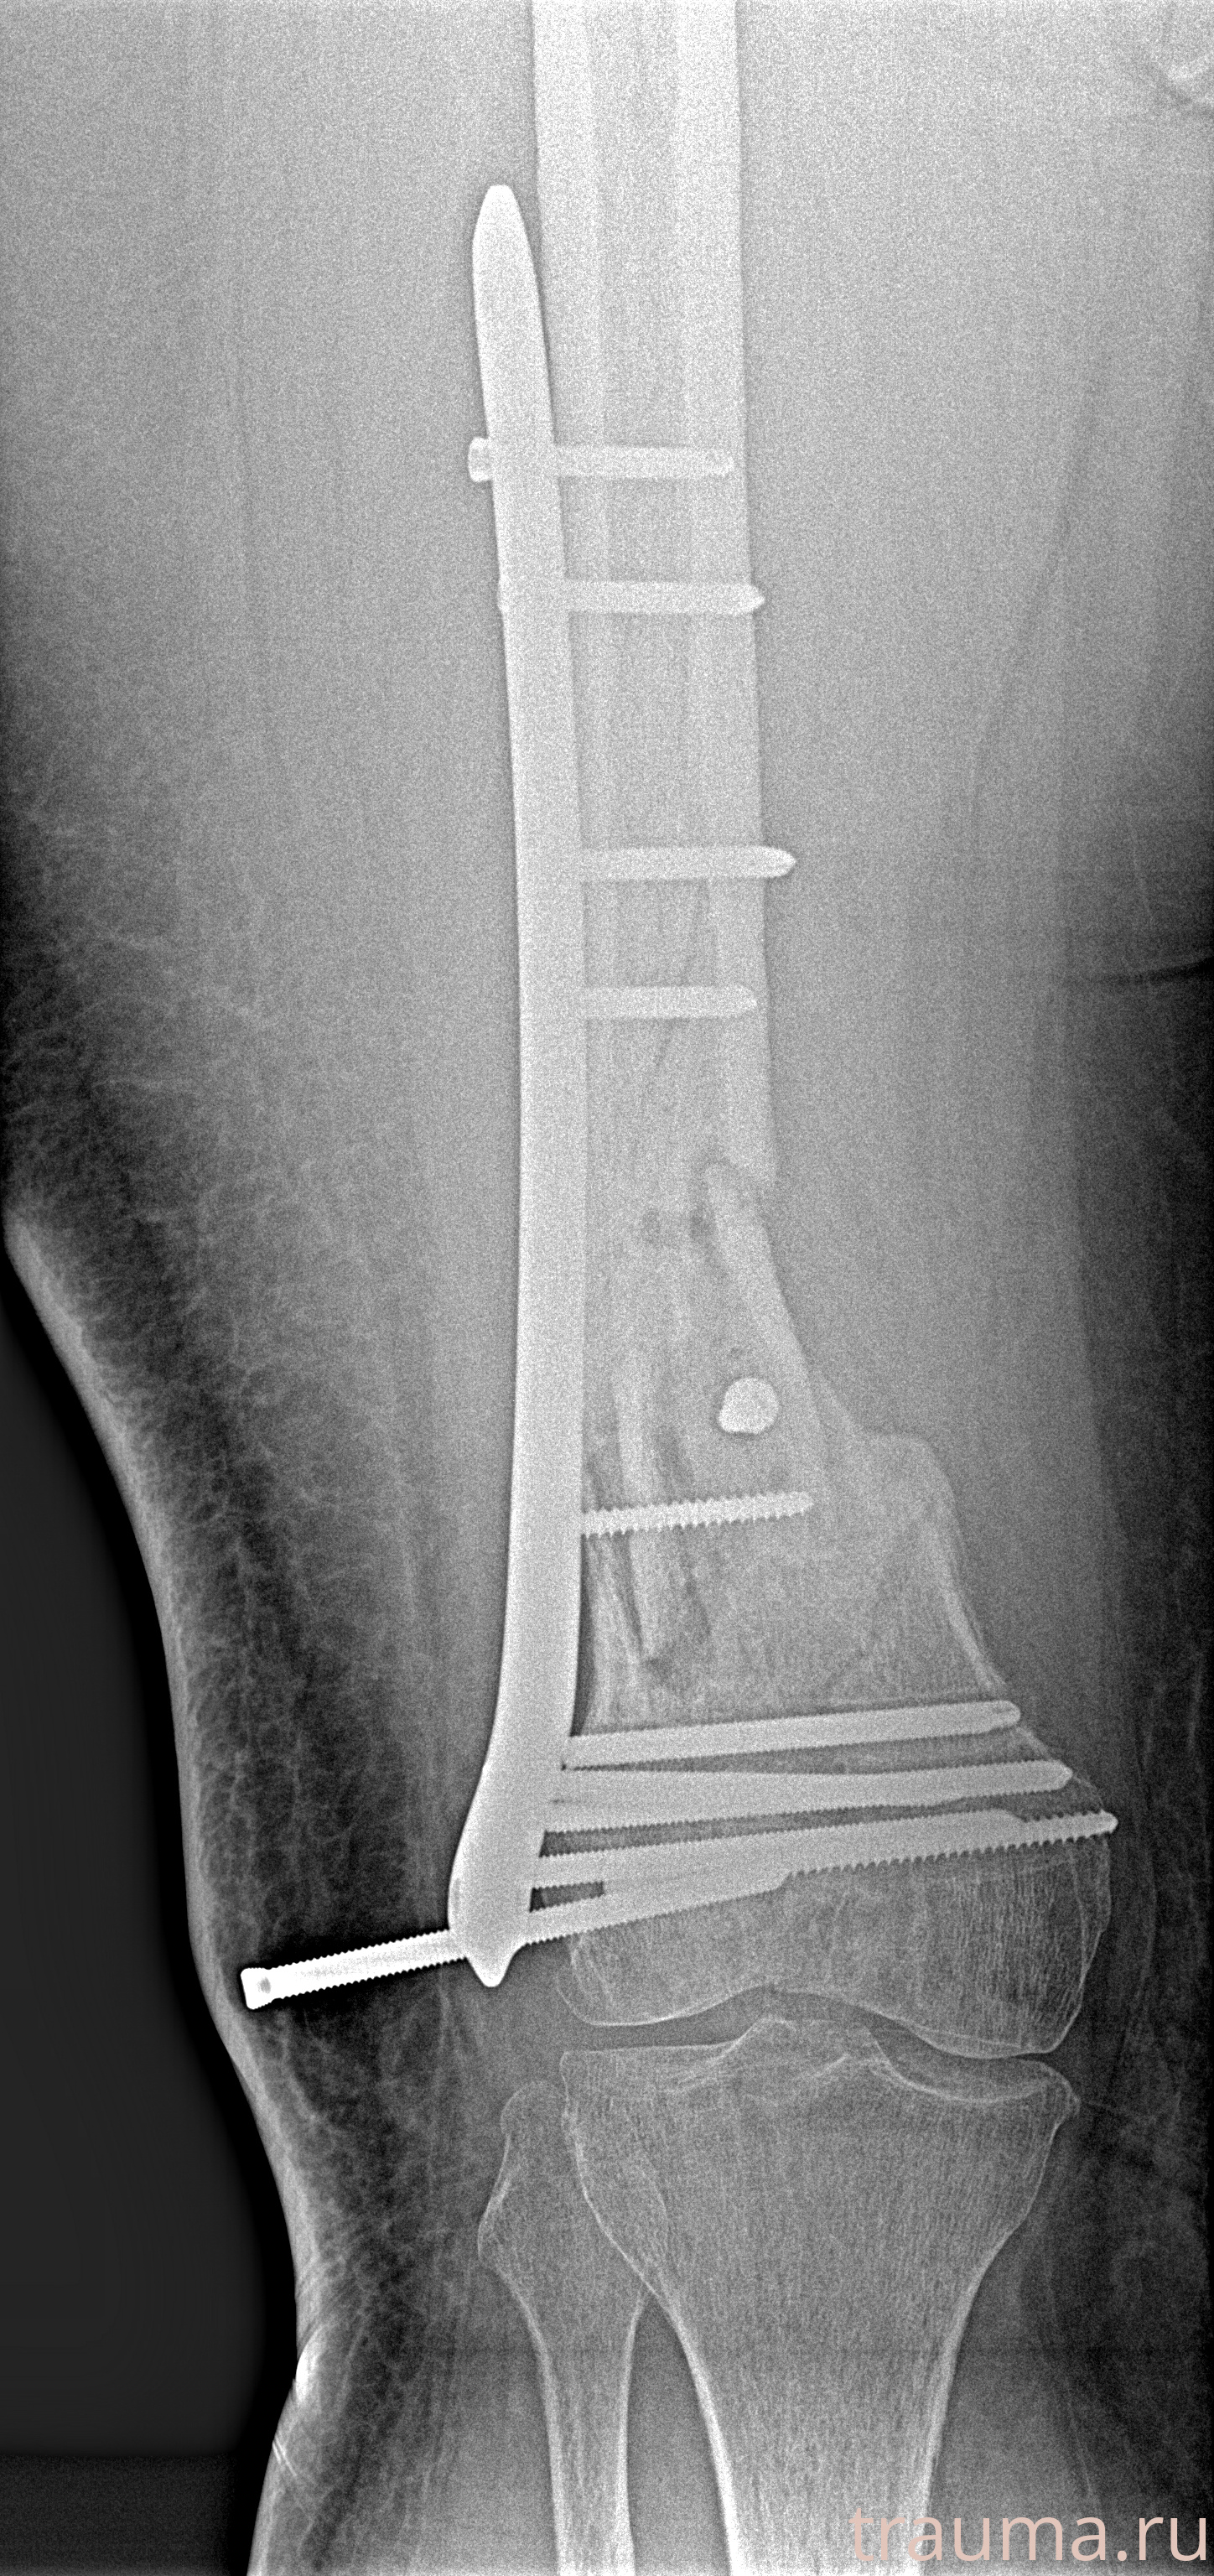

Рентгенограммы

Рентген на дому: по вашему адресу приезжает врач-рентгенолог, травматолог-ортопед с мобильным рентгеновским аппаратом, проводит диагностику травмы или заболевания, делает необходимые рентгенограммы, дает рекомендации по дальнейшему лечению. Получить качественные снимки в домашних условиях возможно благодаря уникальной методике, разработанной МосРентген Центром для института  Склифосовского